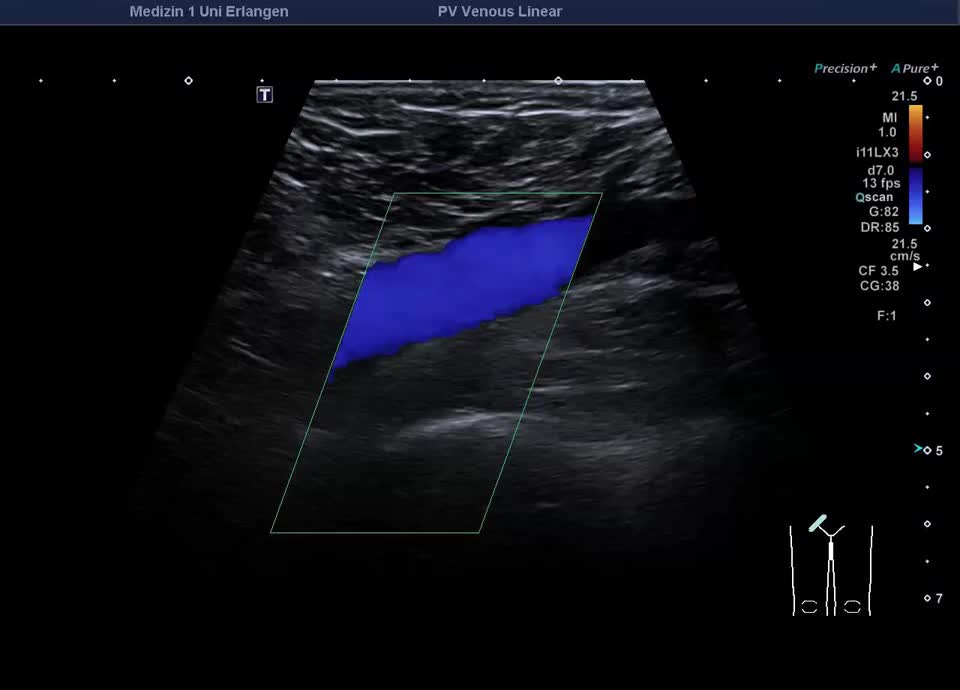

Normalbefunde

• Normalbefund V. femoralis communis rechts (Video)